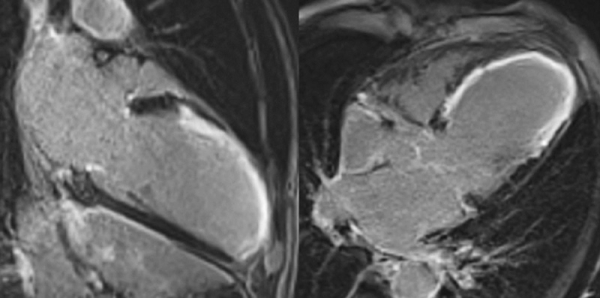

Figure 3A : Séquence de rehaussement tardif - coupe petits-axe

Figure 3B : Séquence de rehaussement tardif - coupes long-axe 4 cavités et 2 cavités

Figure 3A : Séquence de rehaussement tardif - Coupes petit-axe

Présence d’un large rehaussement tardif sous-endocardique de 8 à 9 segments sur 17 avec un réhaussement transmural (100% de transmuralité) dans la quasi-totalité des segments. Ainsi, si l’IRM cardiaque avait été réalisée à plus de 4 semaines de la phase aiguë nous aurions pu conclure avec certitude à une absence de viabilité.

Cependant, le fait d’être à seulement 2 semaines de la phase aiguë ne nous permet pas de conclure avec certitude à la non-viabilité de cet IDM

Enfin, bien que l’amincissement de la paroi (< 6 mm dans les recommandations en échocardiographie) et l’akinésie soit très en faveur d’une absence de viabilité, plusieurs études ont montré que certains patients pouvaient malgré tout présenter un IDM viable (avec alors un rehaussement tardif < 50% sur l’IRM réalisée à plus de 4 semaines de la phase aiguë).

Aucun thrombus intra-VG n’est visualisé sur ces séquences de rehaussement tardif. Un thrombus serait apparu sous la forme d’une masse en hyposignal (noire) au niveau de l’apex VG par exemple.